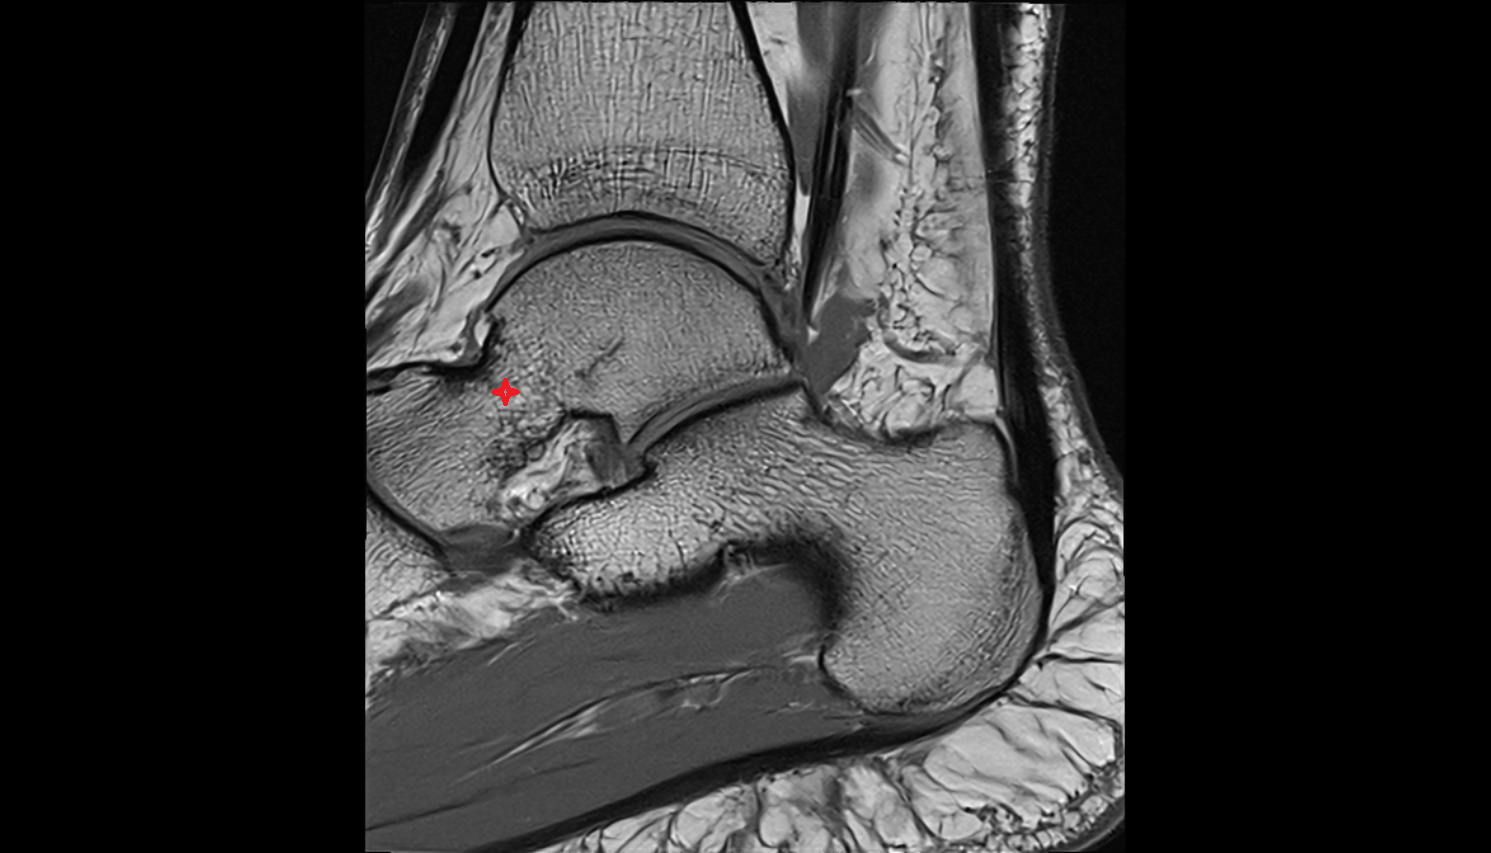

- Talus

- Head of talus

- Body of talus

- Neck of talus

- Calcaneus

- Ankle joint

- Talocalcaneal joint